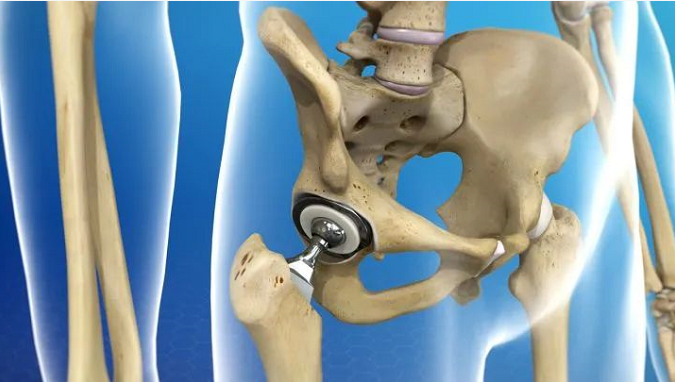

其實,運用最廣泛的實際上是矯形外科(orthopedic)中的關節(jié)置換,生物陶瓷材料作為金屬植體的涂層,增加其生物相容性 (Hench 1991; Jefferies 2014)。